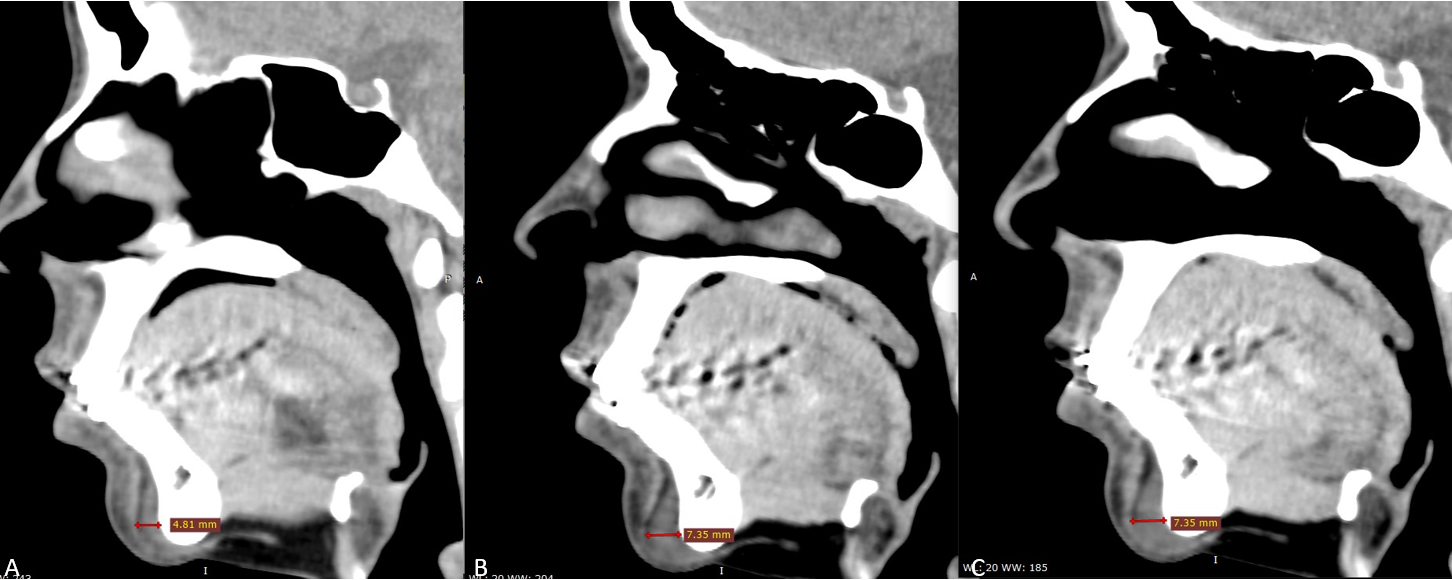

Данные МСКТ: на сагиттальных срезах подбородочной области (рис. 9) определяется имплантат, интимно прилежащий к подбородочному отделу нижней челюсти сзади и к подбородочной мышце спереди, в виде включений плотностью аналогичной плотности мышечной ткани. В динамике отмечается увеличение толщины филлера с 4,8 мм до 7,4 мм, миграции и признаков инкапсулирования препарата не выявлено.

Рис. 9

МСКТ сканы подбородочной области, сагиттальная проекция

А – до инъецирования, толщина имплантата 4,8 мм

В – сразу после инъецирования, толщина имплантата 7,4 мм

С – через 3 недели, толщина имплантата 7,4 мм